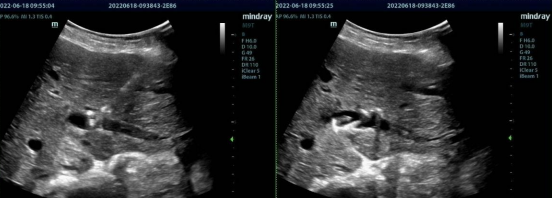

近日,我科与肝胆外科联合成功完成一例高难度超声引导下经皮肝穿刺胆道置管(PTCD)术。

彭老太现年85岁,右上腹疼痛伴皮肤黄染3+天,MRI检查显示肝内胆管广泛扩张,右肝内胆管少许结石,肝门区结构不清,胆总管显示不清,考虑肝门区胆管癌可能。MRCP检查右肝内胆管充盈缺损,肝内胆管广泛扩张,肝门区胆管纠集,胆总管显示不清。经充分术前评估,外科团队决定为其行超声引导下PTCD术。PTCD术对肝内胆管穿刺精准度要求高,超声引导下PTCD术,实时全程精准引导,耗时短,成功率较高,无辐射危害,在临床中治疗中收到青睐。

在超声精准引导下,我科实时多切面扫查选择最佳进针路径并避开周围血管,穿刺针穿入胆管内,穿入导丝,顺利进入胆管,置入引流管,拔出导丝,回抽棕黄色胆汁5ml,固定引流管,复查引流管在胆管内,术后患者无不适,休息后返回病房。